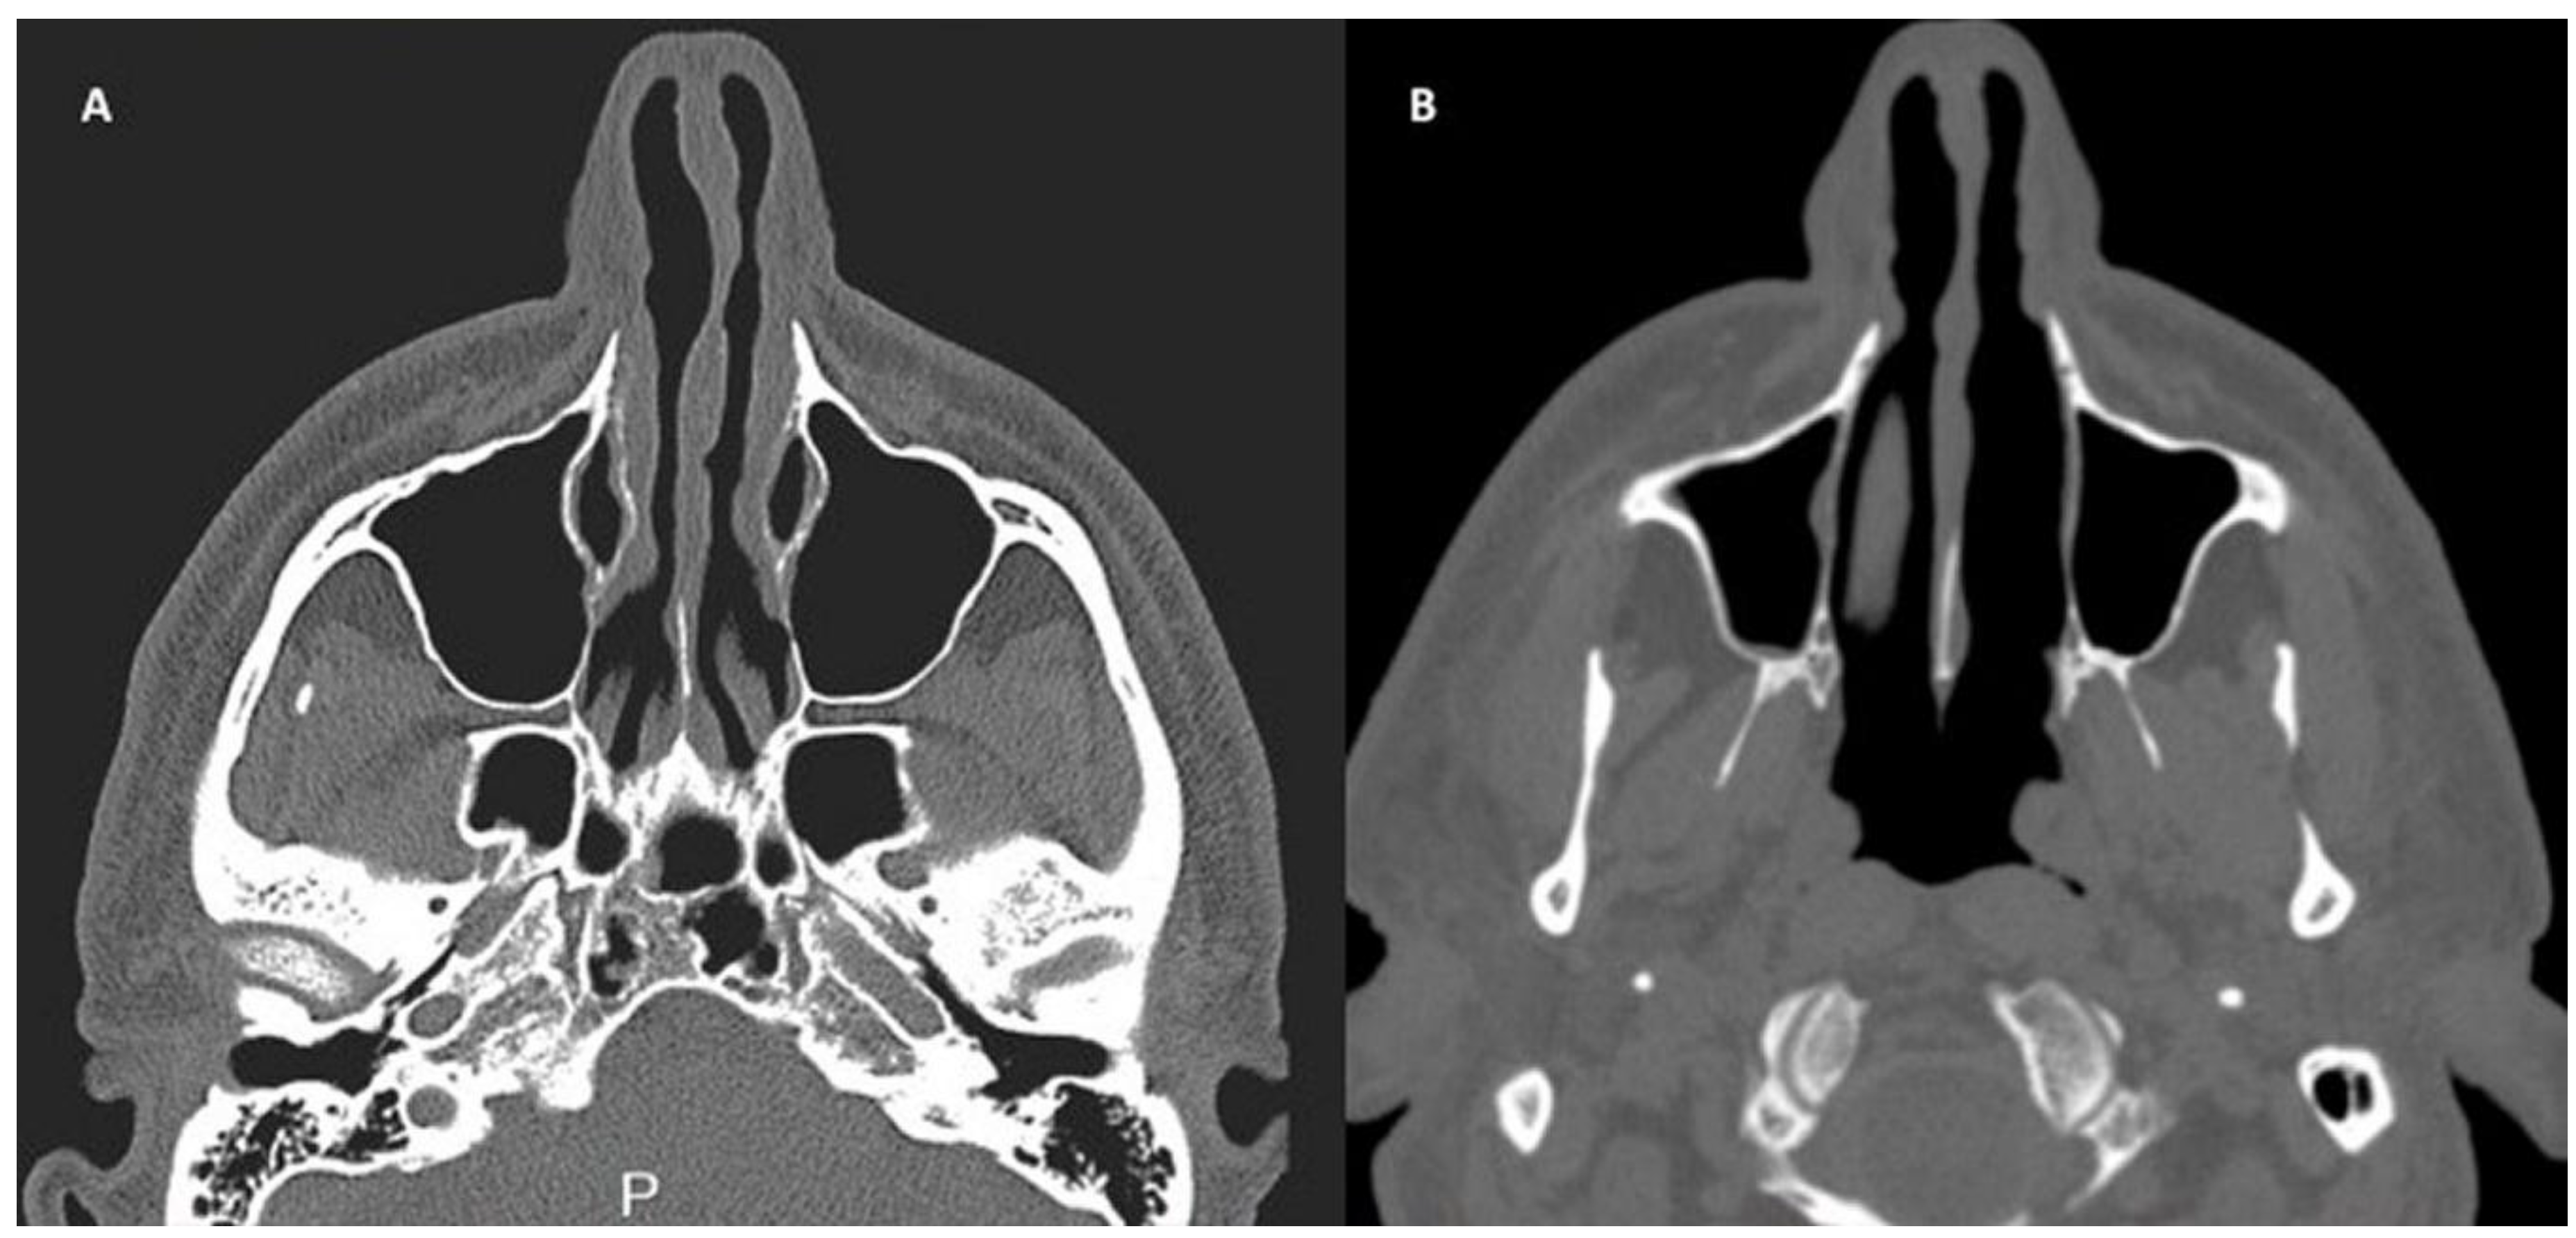

2.4. Patients and Clinical Procedure